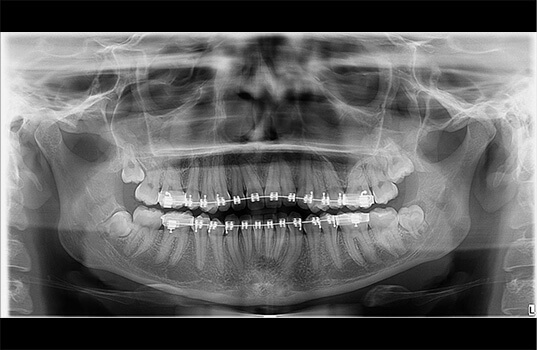

A Radiografia Panorâmica é uma radiografia de boca que fornece uma visão ampla dos dentes, mandíbula e maxila. É usada na odontologia para ajudar a identificar problemas dentários, como cáries, infecções, fraturas e outros problemas ósseos. Além disso, a Radiografia Panorâmica também pode ser usada para planejar tratamentos dentários, como a colocação de próteses e implantes dentários, como também para avaliar o desenvolvimento de tratamentos já realizados.

Na Radiografia Panorâmica, o paciente é posicionado na máquina de Raio-X e precisa ficar parado por alguns segundos enquanto a máquina faz a imagem. A imagem resultante mostra uma visão ampla da boca, mandíbula e maxila, permitindo aos dentistas visualizarem as estruturas ósseas e dentárias de uma só vez.